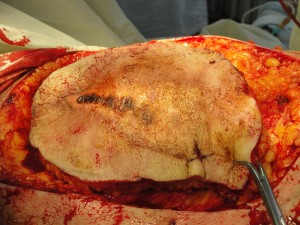

Проведено широкое иссечение раны в пределах неизмененных тканей радиоволновым методом Surgitron, гемостаз. В области дна раневого дефекта, диаметром до 3 см. предлежит и прощупывается гребень большеберцовой кости, что является показанием к закрытию раны васкуляризированным лоскутом. После дессекции и выделения намеченный лоскут, размерами 3х10 см поднят, проведена визуализация перфорантного сосуда, формирующего питающую ножку PPPF (Рис 13). Сам лоскут ротирован аксиллярно на 180 градусов (Рис 14), где адаптирован к краям раневого дефекта и фиксирован узловыми швами (Викрил-плюс 4�).

Рис. 12. Цифровое интраоперационное фото раневого дефекта после иссечения раны и полной дессекции кожно-фасциального островкового лоскута (слева).

Рис. 13. Цифровое интраоперационное фото раневого дефекта после визуализации перфорантного сосуда, питающего кожу и ротирования самого лоскута на 180 градусов (справа).

Края раны в реципиентной зоне сопоставлены с кожными краями лоскута и ушиты, дефект донорской зоны закрыт путем сближения краев и наложением линейного шва без натяжения кожи (Рис. 15). Послеоперационное течение гладкое. После заживления раны выписан к труду на 14 сутки после операции. После радикальной экстирпации раны на голени путем пластики PPPF сформирован устойчивый кожный покров, максимально близкий по структуре и цвету утраченному вследствие травмы.